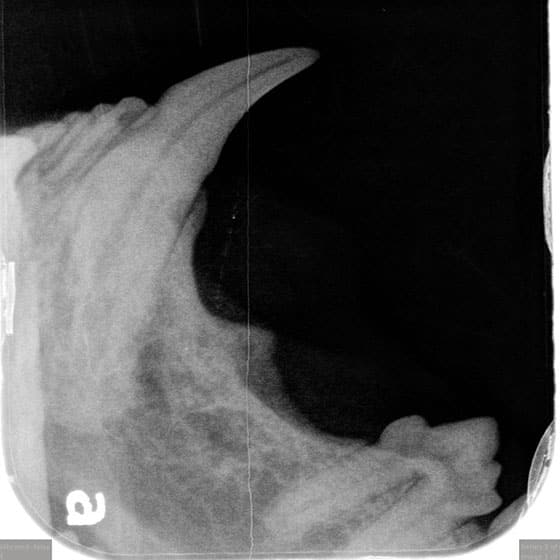

Dental Radiographs (X-rays):

- X-rays are crucial for diagnosing issues not visible to the naked eye, such as tooth root abscesses, bone loss, or retained roots. They guide our treatment plan for optimal outcomes.

Anatomy:

- Pets have smaller mouths, making access to back teeth difficult. The unique structure of pet teeth, differing from human teeth, requires specialized tools and techniques.